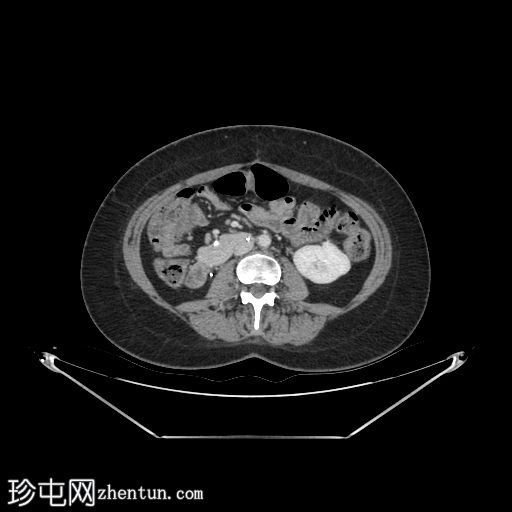

轴位

平扫

自体肾脏和胰腺(胰头、胰体和胰尾)明显萎缩。

移植的胰腺位于右侧腹膜后间隙,大小和形态(轴位、冠状位和矢状位)均正常,可见相关手术缝合线。供体十二指肠段与自体十二指肠吻合。可见胰腺移植物与右髂血管的动脉吻合,胰腺实质强化均匀,提示移植物灌注良好。

左髂窝肾移植(轴位、冠状位),显示移植肾与同侧髂总血管的动脉和静脉吻合。移植肾形态完整,实质均匀强化。

本例中,影像学检查显示原位肾脏和胰腺明显萎缩,符合长期糖尿病合并慢性肾脏病的表现。肾移植位于左髂窝,与同侧髂血管的动脉和静脉吻合通畅,肾实质均匀强化,这些影像学表现均符合功能性肾移植的影像学特征。移植胰腺位于右侧腹膜后,形态和位置均符合原位胰腺,供体十二指肠袢与原位十二指肠吻合良好。